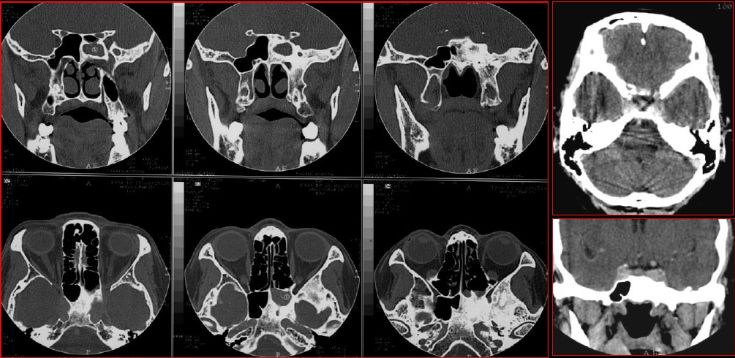

慢性多发鼻窦炎鼻息肉

慢性多发鼻窦炎—MRI